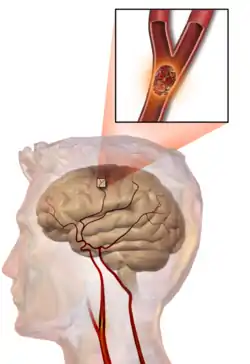

One of the top causes of death worldwide, strokes are disruptions of the blood supply to the brain. These disruptions can be triggered by a variety of ways, the most common of which are the rupturing of an artery (or hemorrhage), or blockages, which may either by from clots or other obstructions. Whatever the immediate cause, obstruction of the vascular system delivering blood to the brain can quickly lead to the death of cells in the affected areas. Like traumatic brain injury, the exact symptoms and consequences of a stroke depends on the region most affected, however there are some common characteristics. Paralysis or weakness on one side of the body- usually manifested in slurring of speech or drooping of the face- is very common since usually the blocked artery will be responsible for delivering blood to one specific brain hemisphere.

If medical attention is not administered quickly enough or if the stroke is severe enough, the damage to the brain may be permanent and can easily cause coma, paralysis, or death. Even if these more extreme consequences are avoided, in many cases the brain is unable to make a full recovery of the injured region and thus cognitive and functional deficits may remain. These can be seen in difficulties in coordinating fluid movement, psychological changes, or trouble with speech. Most of these areas however are at least somewhat amenable to therapy and may be recovered provided the damage was not too severe.

Several experimental therapies are being investigated or are already in place that address the challenges surrounding treating a patient who has experienced a stroke. Some are acute treatments aimed at clearing the obstruction in the arteries to get blood returning as quickly as possible and thus minimize cell death and the functional problems resulting from it, while others are rehabilitation regimens that try to restore lost capabilities. Although neuronal death can in many cases be slowed, there still does not exist any completely effective therapy for recovering lost brain areas in the case of severe strokes.